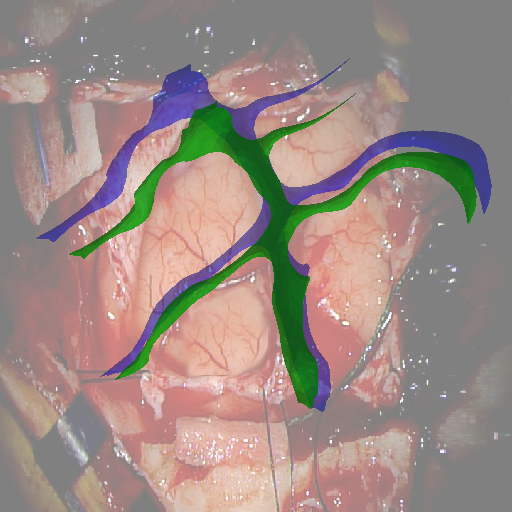

Fig. 5 shows our results as Augmented Reality views with bounding boxes and overlaid meshes. Our method produced visually consistent alignments for all 6 clinical cases without the need for initial registration. Because our current method does not account for brain-shift deformation, our method produced some misalignment errors. However, in all cases, our predictions are similar to the ground truth.